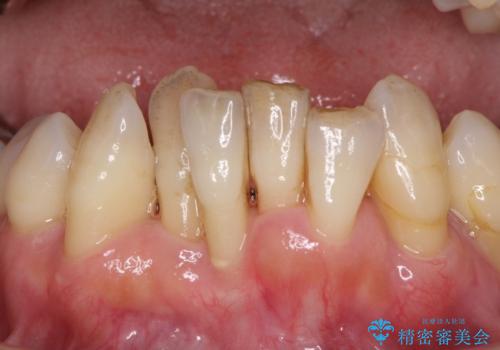

診察を行ったところ、重度歯周病の状態の上に上下の歯列が著しい叢生という状態でした。

歯周初期治療として抜歯や歯槽骨再生治療を行い、さらに歯周ポケット除去を行った後に矯正治療で歯列を整えて行くこととしました。

2~3年は早く終了する予定でしたが、途中で体調を崩されて来院されない時期が続いたため、非常に長期間の治療となりました。

上顎口蓋からの堅い歯肉を移植する角化歯肉移植術を行いたかったのですが、体調不良から実施しなかったため、最終補綴物であるオールセラミッククラウンを装着した後に、知覚過敏や境目が見てしまうといった問題が一部で発生いたしました。